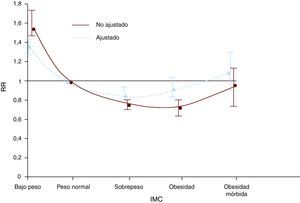

La paradoja de la obesidadLa relación entre el IMC y la incidencia de enfermedad coronaria es directa y su gráfica tiene forma de J. Sin embargo, una vez manifestada la enfermedad coronaria, la asociación entre IMC y pronóstico se hace más compleja. Esto se ha definido como la paradoja de la obesidad pues, contra lo que se esperaría, diversos estudios han demostrado que sujetos con enfermedad coronaria establecida y sobrepeso u obesidad leve tienen mejor pronóstico que sujetos con peso normal o bajo. Estos hallazgos registrados en informes aislados se confirmaron luego en un metaanálisis que evaluó a más de 250.000 pacientes con enfermedad coronaria (Figura 3)7. Hay que considerar con cautela esos hallazgos antes de concluir que el exceso de grasa corporal no es un factor de riesgo de progresión de enfermedad coronaria o que es un factor protector. Primero, los estudios observacionales que muestran la paradoja no prueban que la pérdida de peso no sea beneficiosa para los obesos con enfermedad coronaria, pues todos los estudios usaron solamente el valor de peso corporal de base en el análisis, sin datos de seguimiento. Existen otras asociaciones paradójicas en individuos con enfermedad coronaria, como es el caso de los fumadores71. Se ha demostrado que los fumadores tienen mejor pronóstico después de un infarto de miocardio que los que nunca han fumado72. Sin embargo, se ha demostrado también que los fumadores tienen grados bajos de enfermedad coronaria porque generalmente tienen enfermedad de un solo vaso73. Además, los fumadores que dejan el hábito tienen mucho mejor pronóstico que los fumadores que nunca lo dejaron74. Así, considerando la paradoja de la obesidad desde la perspectiva de la paradoja del fumador, se puede argumentar que la pérdida de peso podría ser beneficiosa para los obesos con enfermedad coronaria. Esto se pudo comprobar en un estudio observacional de pacientes que hicieron rehabilitación cardiaca, pues los que perdieron peso, independientemente de su peso basal, tuvieron mejor pronóstico que aquellos cuyo peso aumentó o no cambió75.

Figura 3. Riesgo relativo (RR) de mortalidad total ajustada y no ajustada en sujetos con enfermedad coronaria, por grupos de índice de masa corporal (IMC) 7 .

La paradoja de la obesidad se ha explicado de diferentes maneras. Valores bajos de IMC se relacionan con poca masa magra, un estado también conocido como sarcopenia76. Los pacientes con sarcopenia tienen poca resistencia al ejercicio, escaso consumo de VO2 y otras características comúnmente asociadas a mayor mortalidad. Debido a que el IMC no puede diferenciar entre la masa muscular y la grasa, es posible que los sujetos con enfermedad coronaria y sobrepeso moderado u obesidad tengan más masa muscular preservada. Una vez que el IMC llega a valores muy altos, que reflejan mejor la adiposidad corporal77,78,68, la paradoja de la obesidad no existe. Un metaanálisis reciente de nuestro grupo, que usó información individual de pacientes provenientes de cinco cohortes, ha demostrado que la obesidad central en individuos con enfermedad coronaria no muestra ninguna asociación paradójica, sino una relación directa entre obesidad central y mortalidad (datos no publicados). Estos hallazgos también respaldan el concepto de que las medidas de obesidad central son mejores marcadores de riesgo cardiovascular relacionado con la grasa, particularmente en pacientes con enfermedad coronaria.